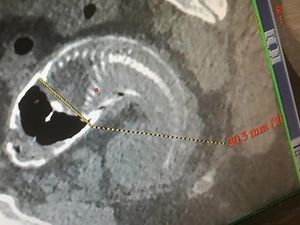

Kejadian unik ada di China. Seorang pria harus dioperasi lantaran ada ikan tilapia yang nyangkut di duburnya. Tak tanggung-tanggung, panjang ikan sekitar 40 cm!